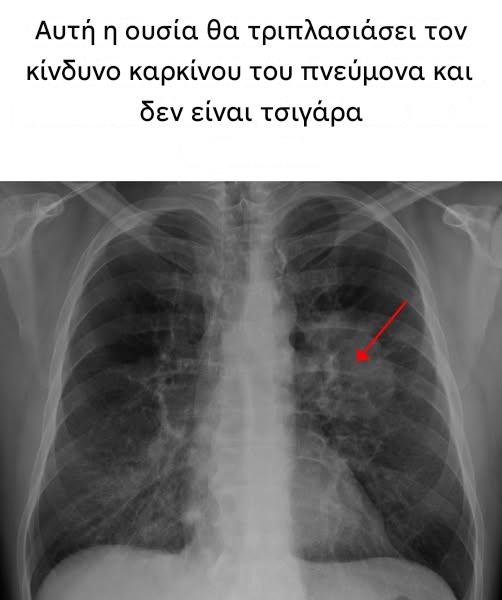

Αυτή η ουσία θα τριπλασιάσει τον κίνδυνο καρκίνου του πνεύμονα και δεν είναι τσιγάρα

Ο ναργιλέ, ένα μείγμα νικοτίνης, ξυλάνθρακα και καπνού, είναι πολύ πιο επιβλαβής για την υγεία από τα τσιγάρα. Μια πρόσφατη μελέτη που διεξήχθη στο Βιετνάμ και δημοσιεύτηκε στο περιοδικό JAMA Oncology δείχνει ότι το κάπνισμα ναργιλέ σχετίζεται με αυξημένο κίνδυνο ανάπτυξης διαφόρων τύπων καρκίνου, συμπεριλαμβανομένου του καρκίνου του πνεύμονα, του ρινοφάρυγγα, του στομάχου και του ήπατος.

Αυτή η μελέτη, η οποία παρακολούθησε περισσότερα από 39.000 άτομα για μια δεκαετία, αποκαλύπτει ότι οι Βιετναμέζοι καπνιστές ναργιλέ εκτίθενται σε κίνδυνο θνησιμότητας από καρκίνο διπλάσιο από ό,τι οι μη καπνιστές, ένα ποσοστό ακόμη υψηλότερο από ό,τι για τους καπνιστές τσιγάρων. Συγκεκριμένα, ο κίνδυνος καρκίνου του πνεύμονα τριπλασιάζεται και ο κίνδυνος καρκίνου του στομάχου τετραπλασιάζεται μεταξύ των χρηστών ναργιλέ.